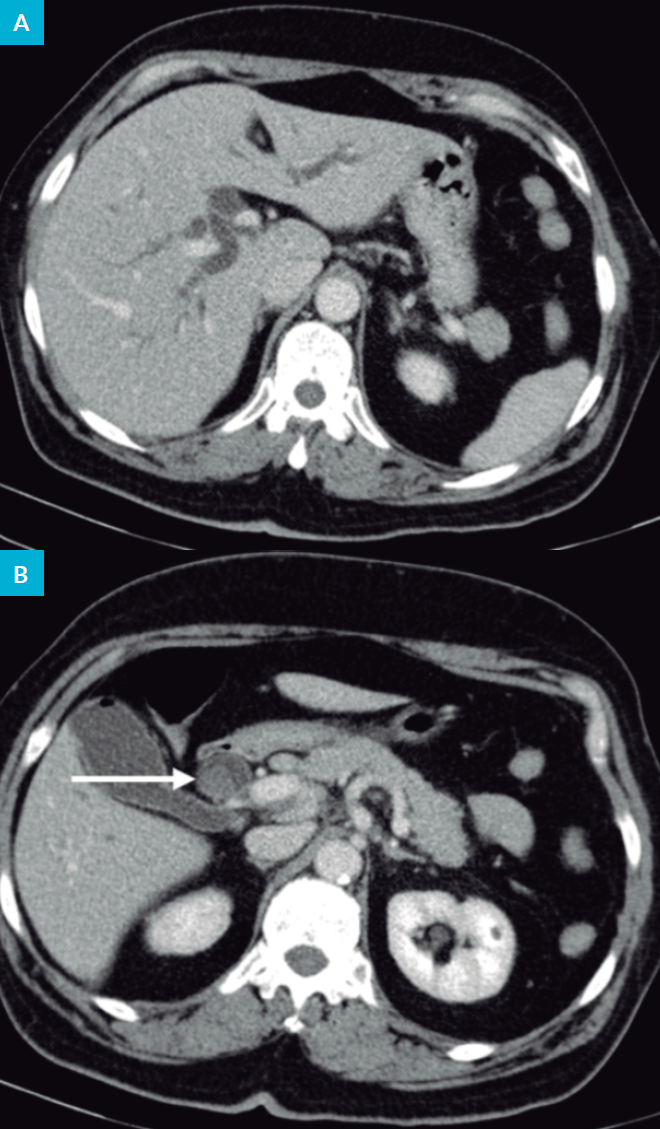

Figura 1: TC abdominal. A - Vias biliares intra-hepáticas dilatadas. B - Cálculo no interior do colédoco (?).

Tomografia computorizada (TC) abdominal: “Dilatação das vias biliares intra-hepáticas (VBIH) e da via biliar principal (VBP) de 18 mm, até ao segmento peri-pancreático/papila. Vesícula biliar em moderada repleção, com parede fina e sem sinais de litíase cálcica. Cálculo no colédoco? Adenomegálias hilares hepáticas e peri-pancreáticas. Fígado, pâncreas e baço sem alterações” (Fig. 1).